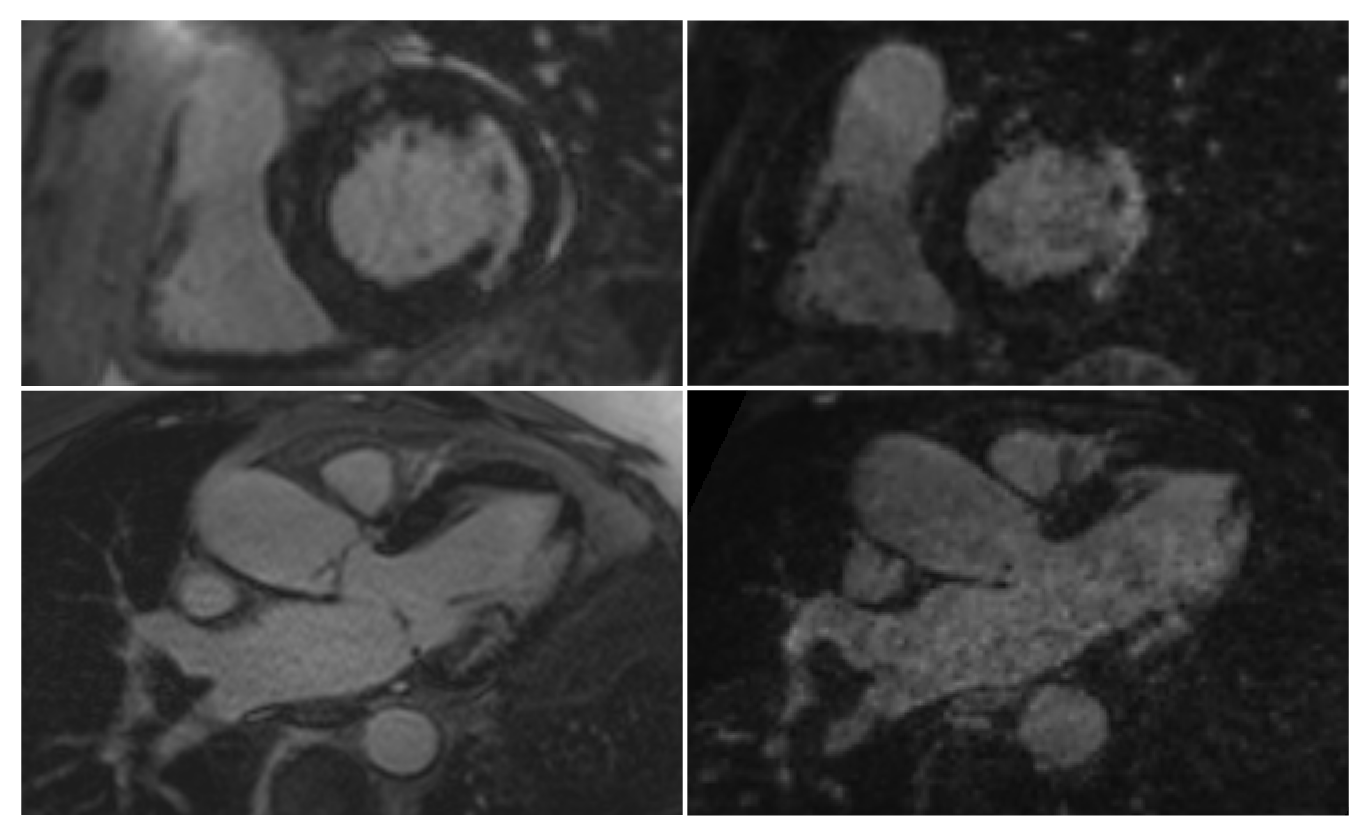

Figure 2: Images showing a comparison between the clinical (left) and proposed (right) scans. One clinical short axis slice and a short axis reformat of the proposed scan are shown top and a similar 3-chamber pair is shown bottom. Both scans show similar patterns of lateral subendocardial enhancement.